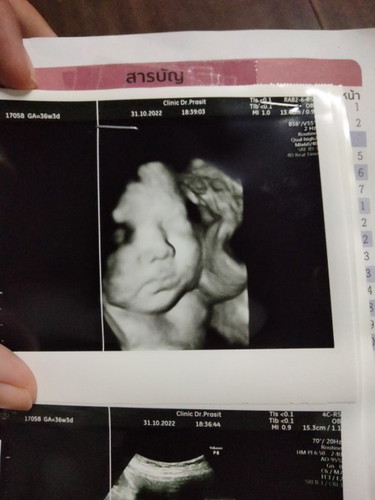

อายุครรภ์ตอนนี้ 36+5W

ตอนนี้ลูกน้ำหนัก3,200 กำหนดคลอดวันที่25 นี้ค่ะ น้ำหนักเยอะเกินไปหรือป่าวค่ะ😁😁#ขอบคุณล่วงหน้านะคะ